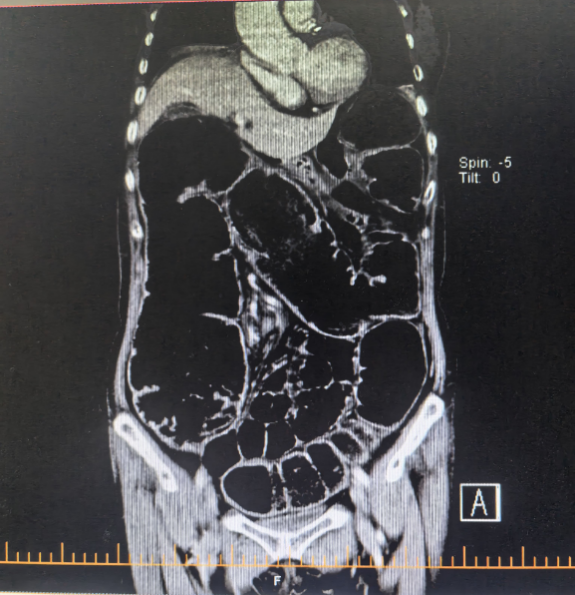

近日,在北京中醫藥大學東方醫院二七院區,一場與時間賽跑的生命救援悄然上演。一位老年患者因“腹部脹痛1月,且近3日無排氣排便”前來就診。經門診腹部 CT 檢查,結果顯示為低位腸梗阻,直腸上段占位可能性極大。

北京中醫藥大學東方醫院二七院區脾胃肝膽科王志斌主任仔細閱片后,高度懷疑患者患有直腸癌。當時,患者腸腔張力極高,被難以忍受的腹脹痛折磨,還伴隨著劇烈的惡心嘔吐,情況十分危急。王主任當機立斷,決定馬上為患者實施腸道支架置入術,以此解除梗阻,緩解腸道壓力。

治療前腹CT示腸腔明顯擴張 治療后立位腹平片示腸道梗阻較前明顯緩解